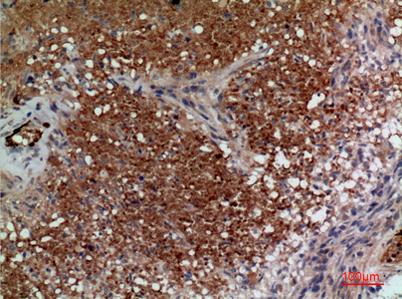

Product name: CD241 rabbit pAb

Dilutions: Western Blot: 1/500 - 1/2000. IHC-p: 1:100-300 ELISA: 1/20000. Not yet tested in other applications.

Immunogen: The antiserum was produced against synthesized peptide derived from the N-terminal region of human RHAG. AA range:1-50

Cellular localization: Membrane ; Multi-pass membrane protein.

Background: The protein encoded by this gene is erythrocyte-specific and is thought to be part of a membrane channel that transports ammonium and carbon dioxide across the blood cell membrane. The encoded protein appears to interact with Rh blood group antigens and Rh30 polypeptides. Defects in this gene are a cause of regulator type Rh-null hemolytic anemia (RHN), or Rh-deficiency syndrome.[provided by RefSeq, Mar 2009],